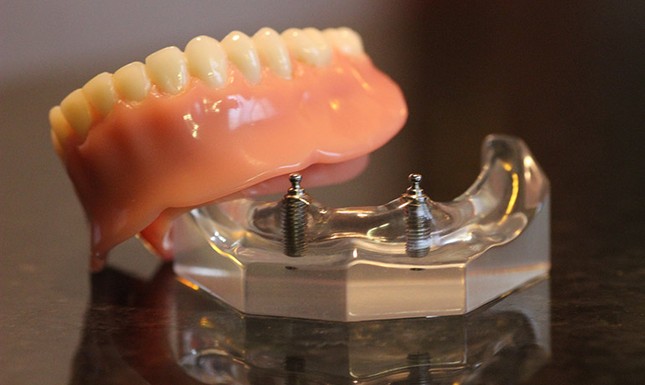

Современные съемные протезы на локаторах: Фото и примеры